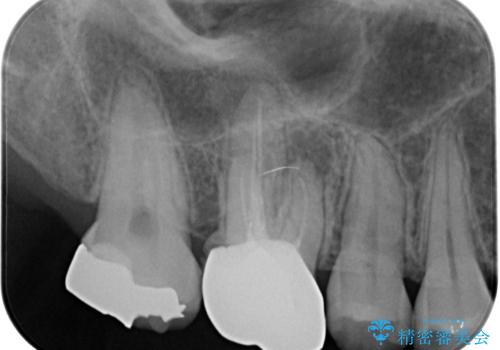

しかし、噛み合わせの相手である右上の第二大臼歯が、長期間噛み合う歯がなかった影響で**挺出(歯が下に伸びてくる状態)してしまっており、このままではインプラントを埋入して被せもの(上部構造)を入れるためのスペースが不足している状態でした。

そこで、右上の奥歯に部分的なワイヤーを装着し、さらに矯正用アンカースクリュー(TADs)を併用することで、挺出した歯を圧下(歯を元の高さに戻す動き)させ、下顎にインプラントを埋入するための十分な垂直的スペースを確保しました。

スペースが整った段階で、右下の第一大臼歯と第二大臼歯にインプラントを埋入。